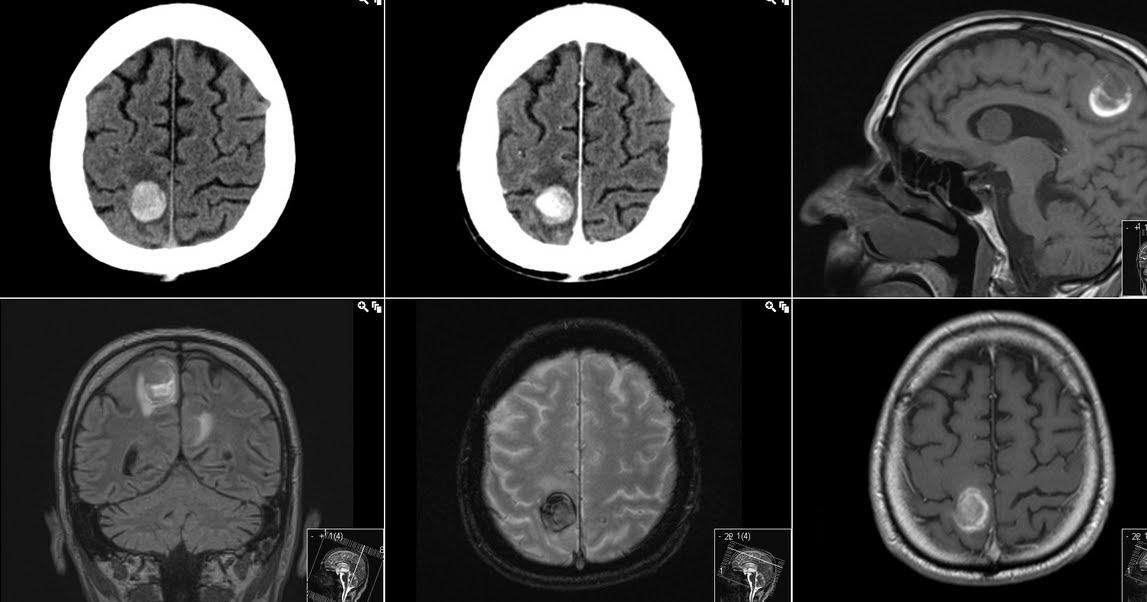

Dr Balaji Anvekar FRCR Hemorrhagic Metastasis MRI Brain

Radiology MRI Hemorrhagic Brain Metastases